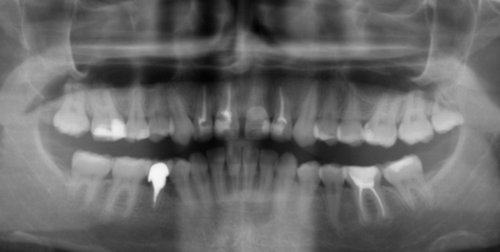

Второй вопрос: Мне вылечили от кариеса семнадцатый и двадцать шестой зубы. Лечение производилось от двух до трех недель назад. До этого жевать было удобно, как твердую, так и мягкую пищу. Сейчас есть мягкую пищу удобно и комфортно, а твердую - не очень. Болей нет, но ощущения не очень приятные. В районе семнадцатого и двадцать шестого, ощущается некий дискомфорт.

С чем это может быть связано?

На снимке в области семнадцатого и двадцать шестого зуба, под пломбой, наблюдается полость, которая неграмотно препарирована перед установкой пломбы, чувствительность и некий дискомфорт при надкусывании или пережевывании твердой пищи связано именно с этим. Что касается шестнадцатого зуба, я считаю, что полость имеется, но все-таки необходим еще и очный прием.